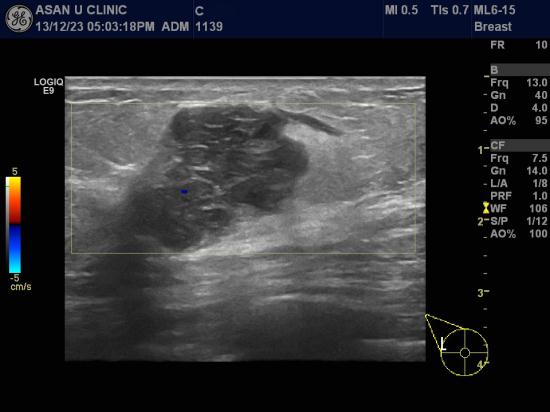

우측유방 외측에 갑자기 만져지는 혹이 있어 내원한 50세 여성분입니다.

본원 유방초음파 통해 3.48cm의 커다란 혹이었으나

여름까지 없다가 갑자기 만져졌다고 합니다.

조직검사상 침윤성 유방암 진단되었고

다행이도 겨드랑이 임파절에는 전이된 조직이 없었습니다.